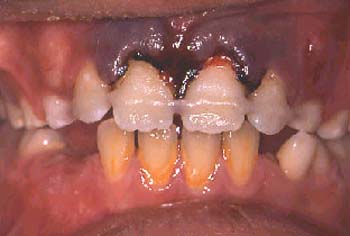

En este caso, el paciente presenta una destrucción periodontal grave del segmento anterior maxilar izquierdo que incluye los incisivos y el canino. El incisivo lateral y el canino tienen un grado 2 de movilidad y una pérdida de masa ósea de más del 60%. El paciente se queja de dolor durante la masticación e incomodidad en los dientes la mayor parte del tiempo.

Se tomó la decisión de ferulizar utilizando composite y la fibra de refuerzo Ribbond. Se realizó este tratamiento debido a la ajustada oclusión y a la necesidad de mantener los contactos oclusales. También, era aconsejable una férula en vestibular porque las fuerzas de oclusión se ejercían sobre la superficie de adhesión.

Se realizó un raspado radicular. Tras la finalización de la terapia inicial periodontal, se llevó a cabo el tratamiento para ferulizar los incisivos y caninos por el traumatismo oclusal secundario.